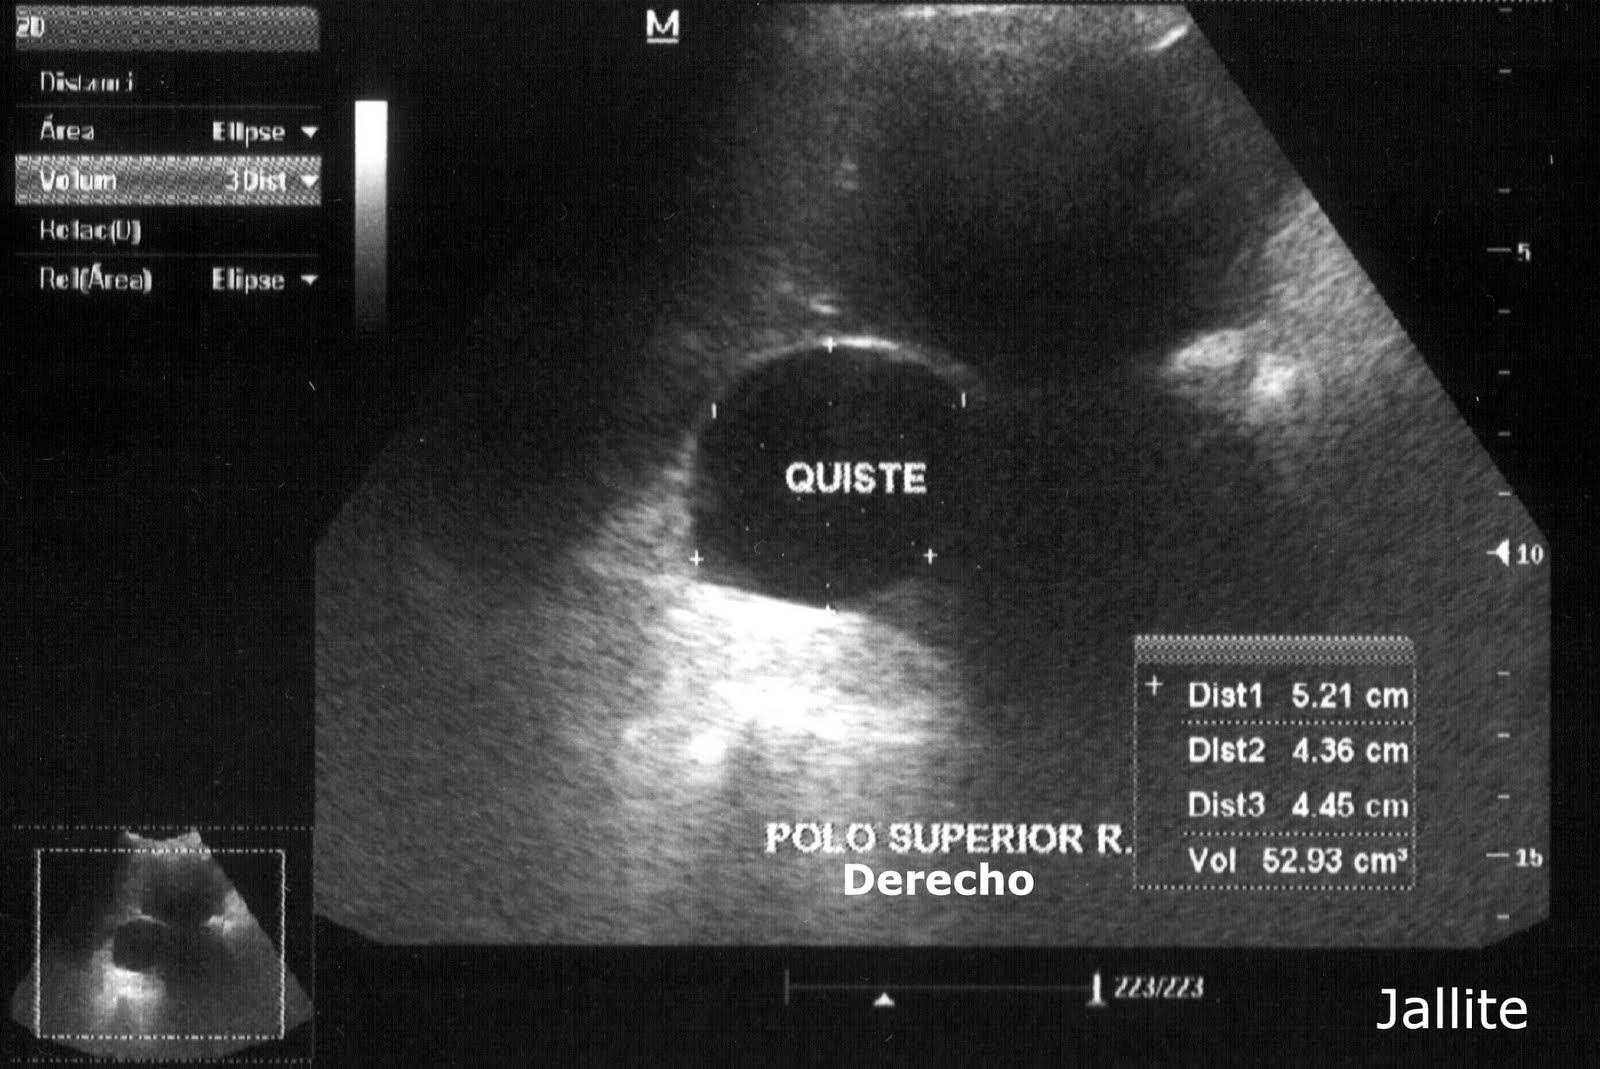

Quiste mesentérico gigante simulador de ascitis intratable Revista de

From www.revistagastroenterologiamexico.org

Quiste mesentérico gigante simulador de ascitis intratable Revista de Que Es Un Quiste En El Estomago Conoce más sobre los síntomas,. Algunos quistes pequeños no causan síntomas; Puede que ni siquiera sepas que. Está ubicado detrás de su estómago y sus enzimas lo ayudan a digerir los alimentos y controlar sus niveles de azúcar en sangre. Un quiste pancreático es un saco cerrado cubierto de epitelio y localizado sobre o dentro de tu. La mayoría de. Que Es Un Quiste En El Estomago.